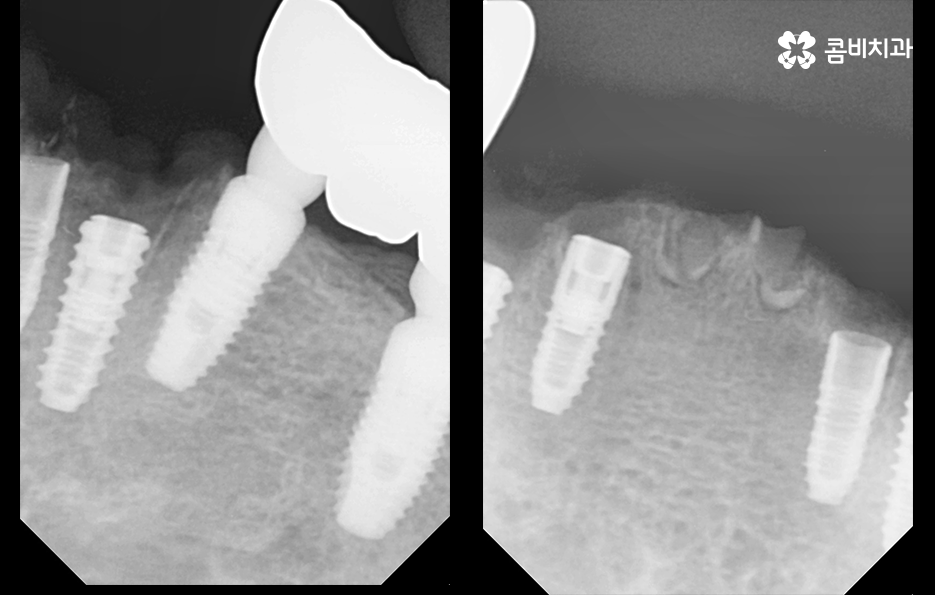

발치후 임플란트 기간에 있어서 뼈이식이 추가 되는 경우에는 뼈이식 기간만 약3~ 6개월을 예상하는 것이 보편적이며 뼈이식을 받은 환자 분들의 경우 골유착 기간 또한 일반적인 임플란트 기간 보다는 좀더 여유있게 회복기간을 지켜보고 있어요. 다만 상태에 따라서 발치 후 뼈이식을 바로 진행하는 경우도 있고, 발치 후 뼈이식과 동시에 픽스처를 식립하여 수술을 진행하는 경우도 있어 정확한 수술 계획은 환자분의 상태에 따라 수술 계획이 달라질 수 있어요.

기본적으로 자연치아나 잇몸 자체의 문제도 복합적인 문제의 양상을 띄는 경우가 대부분이며 임플란트 치료 계획을 세우더라도 잇몸 뼈의 부족으로 인해 뼈이식을 받아야 하는 경우가 많고 임플란트 식립 개수 역시도 여러개를 식립하는 경우가 많다보니 발치후 임플란트 기간에 있어서 넉넉잡아 1년 정도를 치료 기간으로 보고 치료하는 경우도 많이 있어요

또한 이미 치료 후 부작용으로 인해 재수술을 받는 분들도 있기 때문에 재수술 과정에서의 부담은 첫 치료보다 더 크다는 점에서 임플란트의 수명 유지에 대해서도 관심을 많이 갖고 있는데요